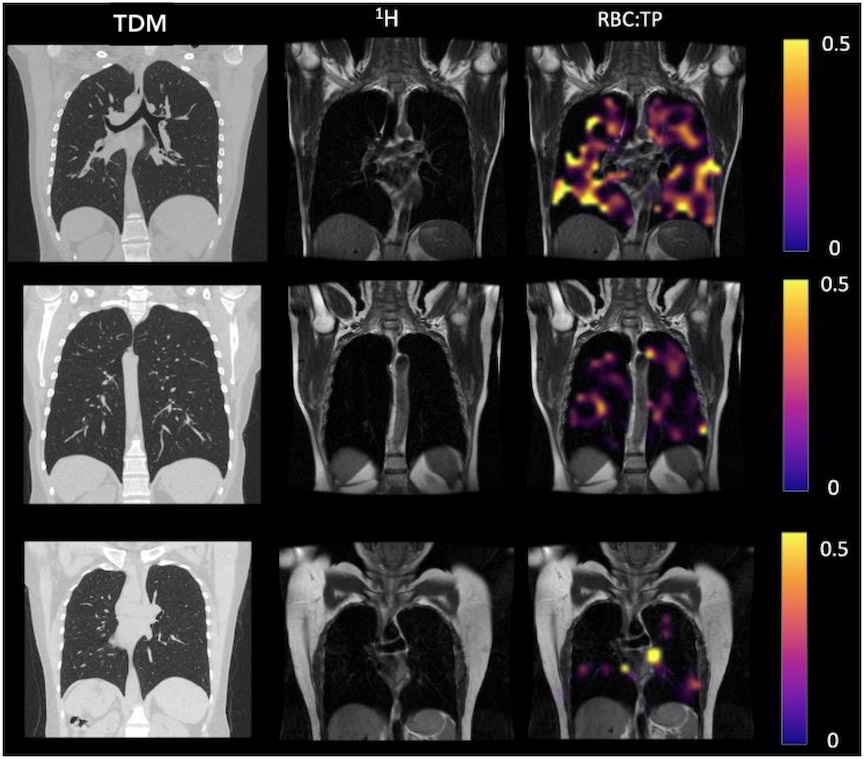

Image radiologique TDM normale du

poumon entrois coupe coronal fenetre parenchymateuse ( à gauche ) ; images IRM normales

du poumon en trois coupe coronal . Et image

radiologique IRM de ventilation de Xenon 129 de même

cas en trois coupe coronal en couleur ( à droit ) |